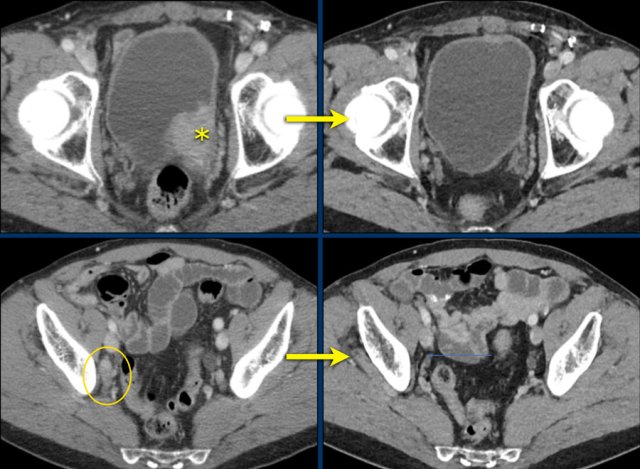

CT-images in a 65-year-old male with bladdercarcinoma and lymph node metastasis (< 15 mm) in the right obturator region.

During treatment with immunotherapy the bladder lesion (target) and lymphadenopathy (non-target) completely disappeared.

This is a complete response.